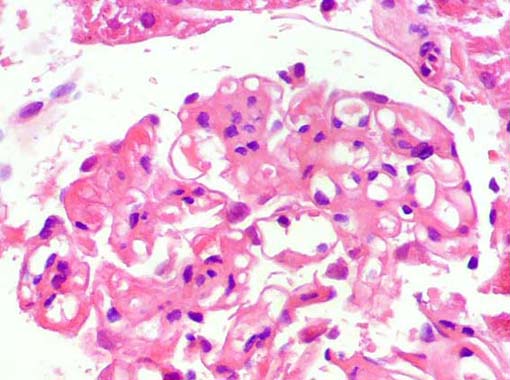

Figura 4.

H&E, X400.